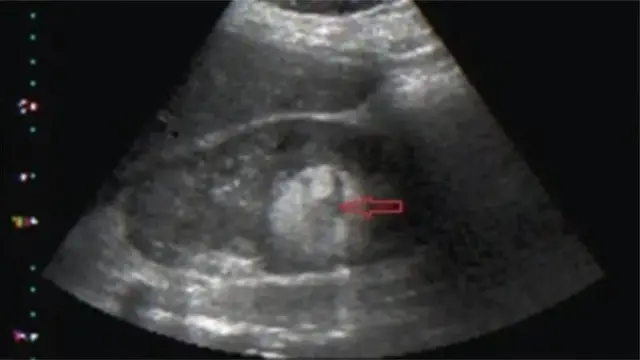

Bi oyun iju naa ba ṣe tobi to, iye to jẹ, ati ibi to wa ninu ile ọmọ, ni yoo sọ ami ti obinrin yoo ri.

Ṣugbọn Dokita Brown sọ pe ọpọlọpọ obinrin to ni oyun iju kii ri ami kankan.